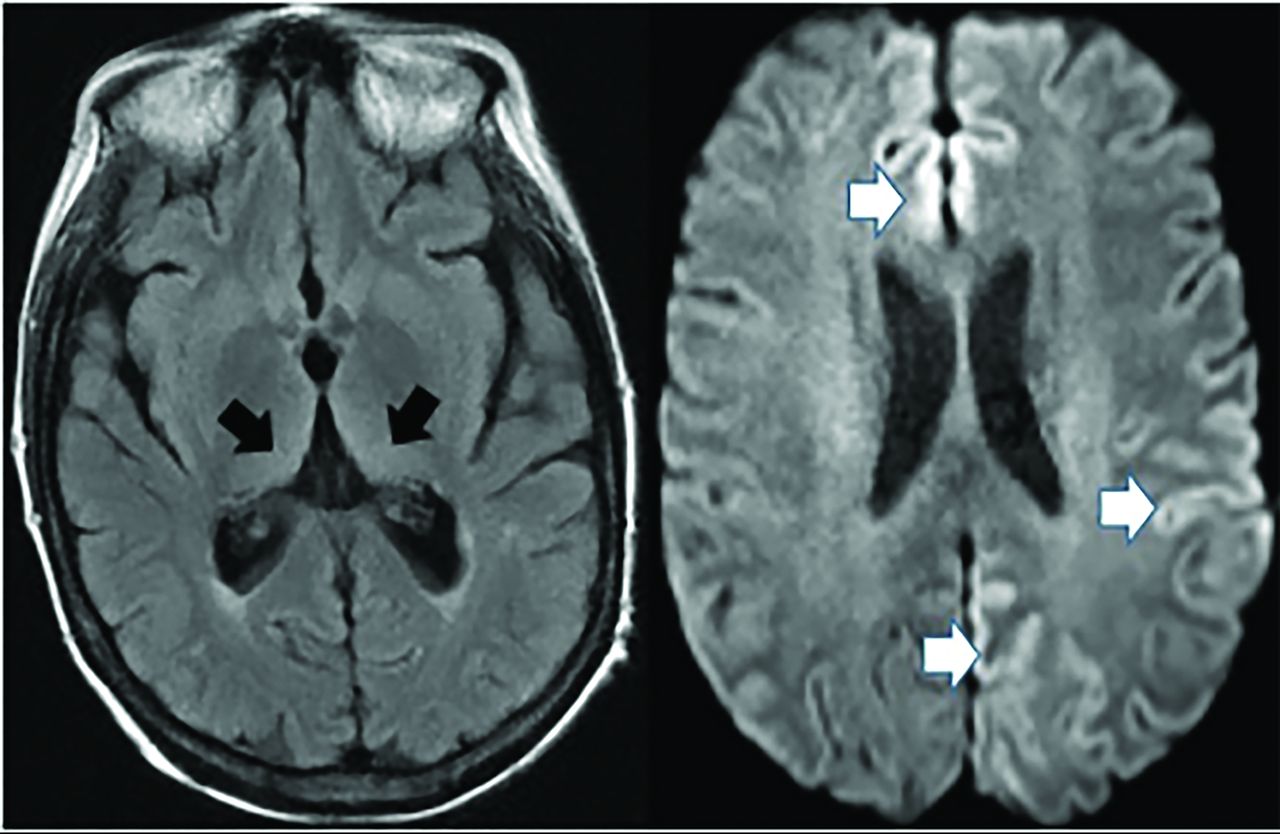

Creutzfeldt-Jakob disease causes rapid cognitive decline from altered prion protein accumulation, producing neurotoxicity and cortical/subcortical spongiform necrosis. On MR imaging, striatum and neocortex increased T2 FLAIR (medial-thalamic hockey-stick configuration) is noted, often also affecting the cortex (Fig 14). SPECT reveals widely inconsistent perfusion variations, and FDG-PET shows cortical and basal ganglia involvement in later stages.61

Creutzfeldt-Jakob disease demonstrates hockey stick configuration (black arrows), medial thalamic increased FLAIR (left axial image) as well as medial frontal, left parietal and occipital cortical increased signal (white arrows) (cortical ribbon sign, right axial image).